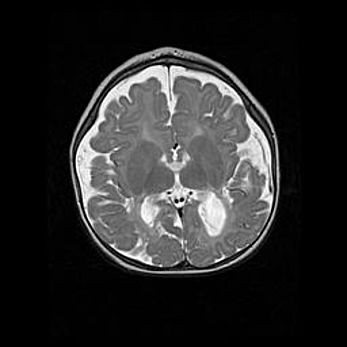

Подострая гематома правой гемисферы мозжечка.

Наружная гидроцефалия.

Возраст: 15 дней

Вес: 3100 г

Пол: женский

Окружность головы: 37 см

Срок гестации: 35-36 недель

При открытой наружной форме гидроцефалии у новорожденных расширяются и переполняются субарахноидные пространства.

Кровоизлияния в мозжечок имеют две клинико-анатомические формы: полушарные гематомы и кровоизлияния в червь.

К появлению этой патологии может привести: повреждения головного мозга, возникающие в результате асфиксии и гипоксии плода при беременности, или травмы во время родов. Редко гематома мозжечка может быть результатом первичной коагулопатии и сосудистой мальформации, диссеминированном внутрисосудистом свертывании, изоиммунной тромбоцитопении.